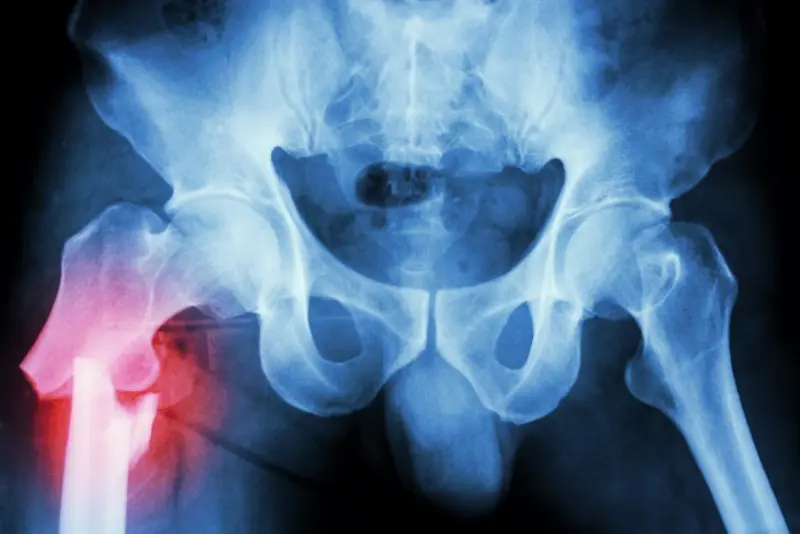

Hoftebrudd er den mest alvorlige følgen av osteoporose. De fleste slike brudd hos eldre skyldes redusert beintetthet kombinert med et fall. I Norge rammes cirka 9000 personer av hoftebrudd hvert år. Det er mange risikofaktorer for både fall og redusert beintetthet, og risiko for å få et brudd kan reduseres ved hjelp av livsstilsendring og bruddforebyggende behandling.